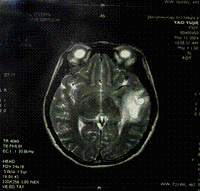

術前B 超、CT、MRI、腹腔穿刺可有助於診斷、血清CA125均為陽性表達。